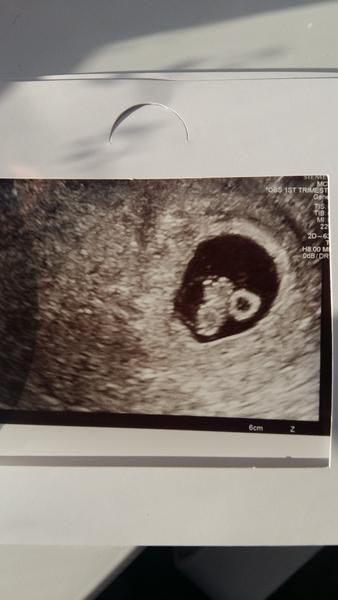

Zienky moje drahé Ďakujem Vám za podporu 🙏 Tak už som domka už ležím, som 7tt+1d a bábätko je v poriadku.Bilo mu srdiečko ❤ Mám síce bolesti ale dám si magnezium a prejde má to hádam.. prikladám aj moju malú lásku 😘😇🤗